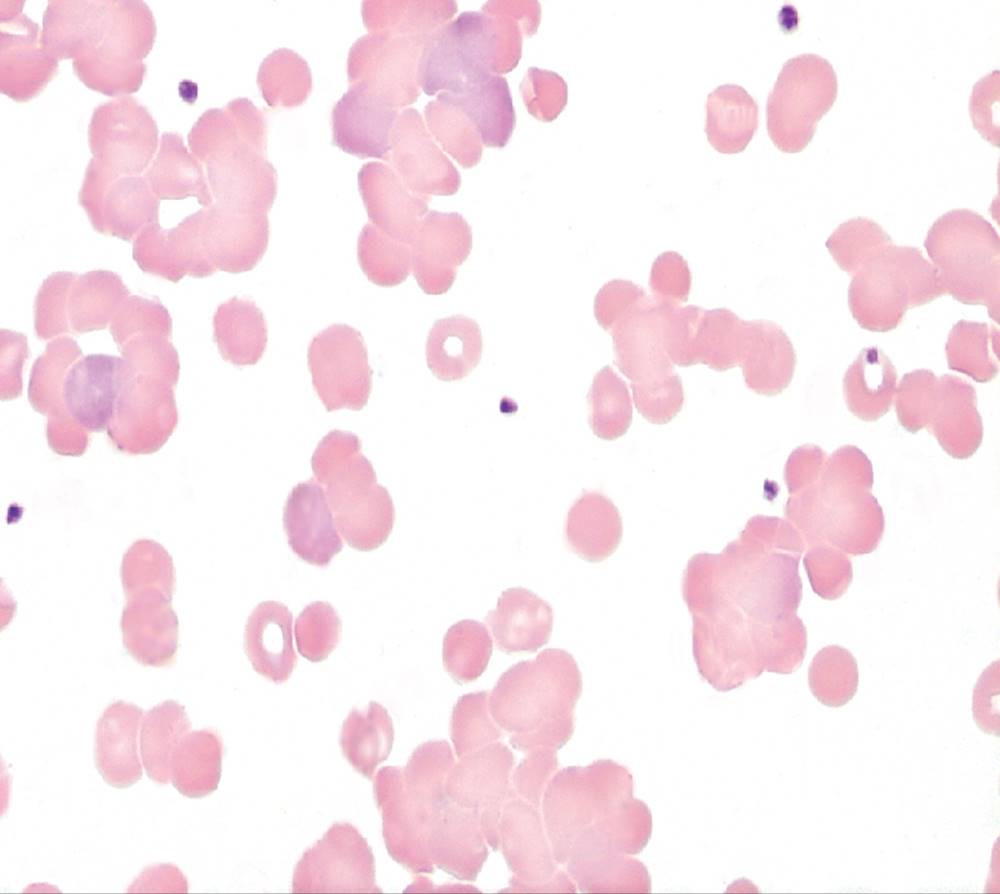

The EKG was normal. The CBC instrument printout flagged for nucleated red blood cells (and corrected the WBC for them), 3+ anisocytosis, and reticulocytosis. The peripheral blood film had moderate spherocytes, moderate polychromasia, few macrocytes, 3+ anisocytosis, and 15 nucleated red blood cells/100 WBCs (Figure 26-1). Occasional schistocytes and neutrophilia with a slight left shift were also observed on the blood film (not shown in figure). The urinalysis report included 2+ protein, 2+ blood, increased urobilinogen, with 0 to 5 RBCs seen on the microscopic exam. The patient’s serum was moderately icteric, and the total serum bilirubin was increased. The patient was admitted for further testing. The serum haptoglobin was decreased, the serum indirect (unconjugated) bilirubin and lactate dehydrogenase (LD) were elevated, and urine hemosiderin was positive.

FIGURE 26-1 Wright-stained peripheral blood film from the patient in the case study (×1000).

Anemia in WAIHA can be mild or severe, with RBC life span sometimes reduced to 5 days or less.1 Laboratory findings for serum and urine reflect the predominantly extravascular hemolysis that occurs in IgG-mediated immune hemolysis. Polychromasia and spherocytes are the typical findings on the peripheral blood film (Figure 26-1). Occasionally the WAIHA is accompanied by immune thrombocytopenic purpura and a decreased platelet count, a condition known as Evans syndrome, which occurs primarily in children.6, 7